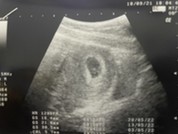

มาสอบถามแม่ๆค่ะ ว่าแม่ๆเห็นตอนน้องตอนกี่สัปดาห์กันคะ ของบ้านนี้6สัปดาห์กว่าน้องยังไม่โผล่มาให้เห็นเลยค่ะ #ท้องแรกคะ

เห็นและได้ยินเสียงหัวใจตอน6 วีคคะ ซาวหน้าท้องไม่เจอ แต่เจอเพราะซาวช่องคลอดคะชัดเจนมาก

ตรวจเมื่อวาน น้อง5วีคกว่าๆ เห้นเเล้วค่ะ หัวใจเต้นเเล้ว

6 สัปดาห์ค่ะ ซาวน์ผ่านช่องคลอด เนื่องจากมีเลือดออก หมอเลยต้องซาวน์ดูเจ้าตัวเล็กค่ะ

บ้านนี้ซาวว์ตอน 5 สัปดาห์อะคะเห็นน้องน้อยเท่าเม็ดถั่วอะคะ

บ้านนี้ไปตรวจตอน6w4d ชาวด์ทางช่องคลอดเจอถุงตั้งครรภ์และหัวใจแล้วค่ะ☺️ ท้องสอง

6wมีแต่ถุวตั้งครรภ์7wเจอไข่แดง8w4dเจอน้องพร้อมเสียงหัวใจค่ะ #ตอนนี้27wแล้ว